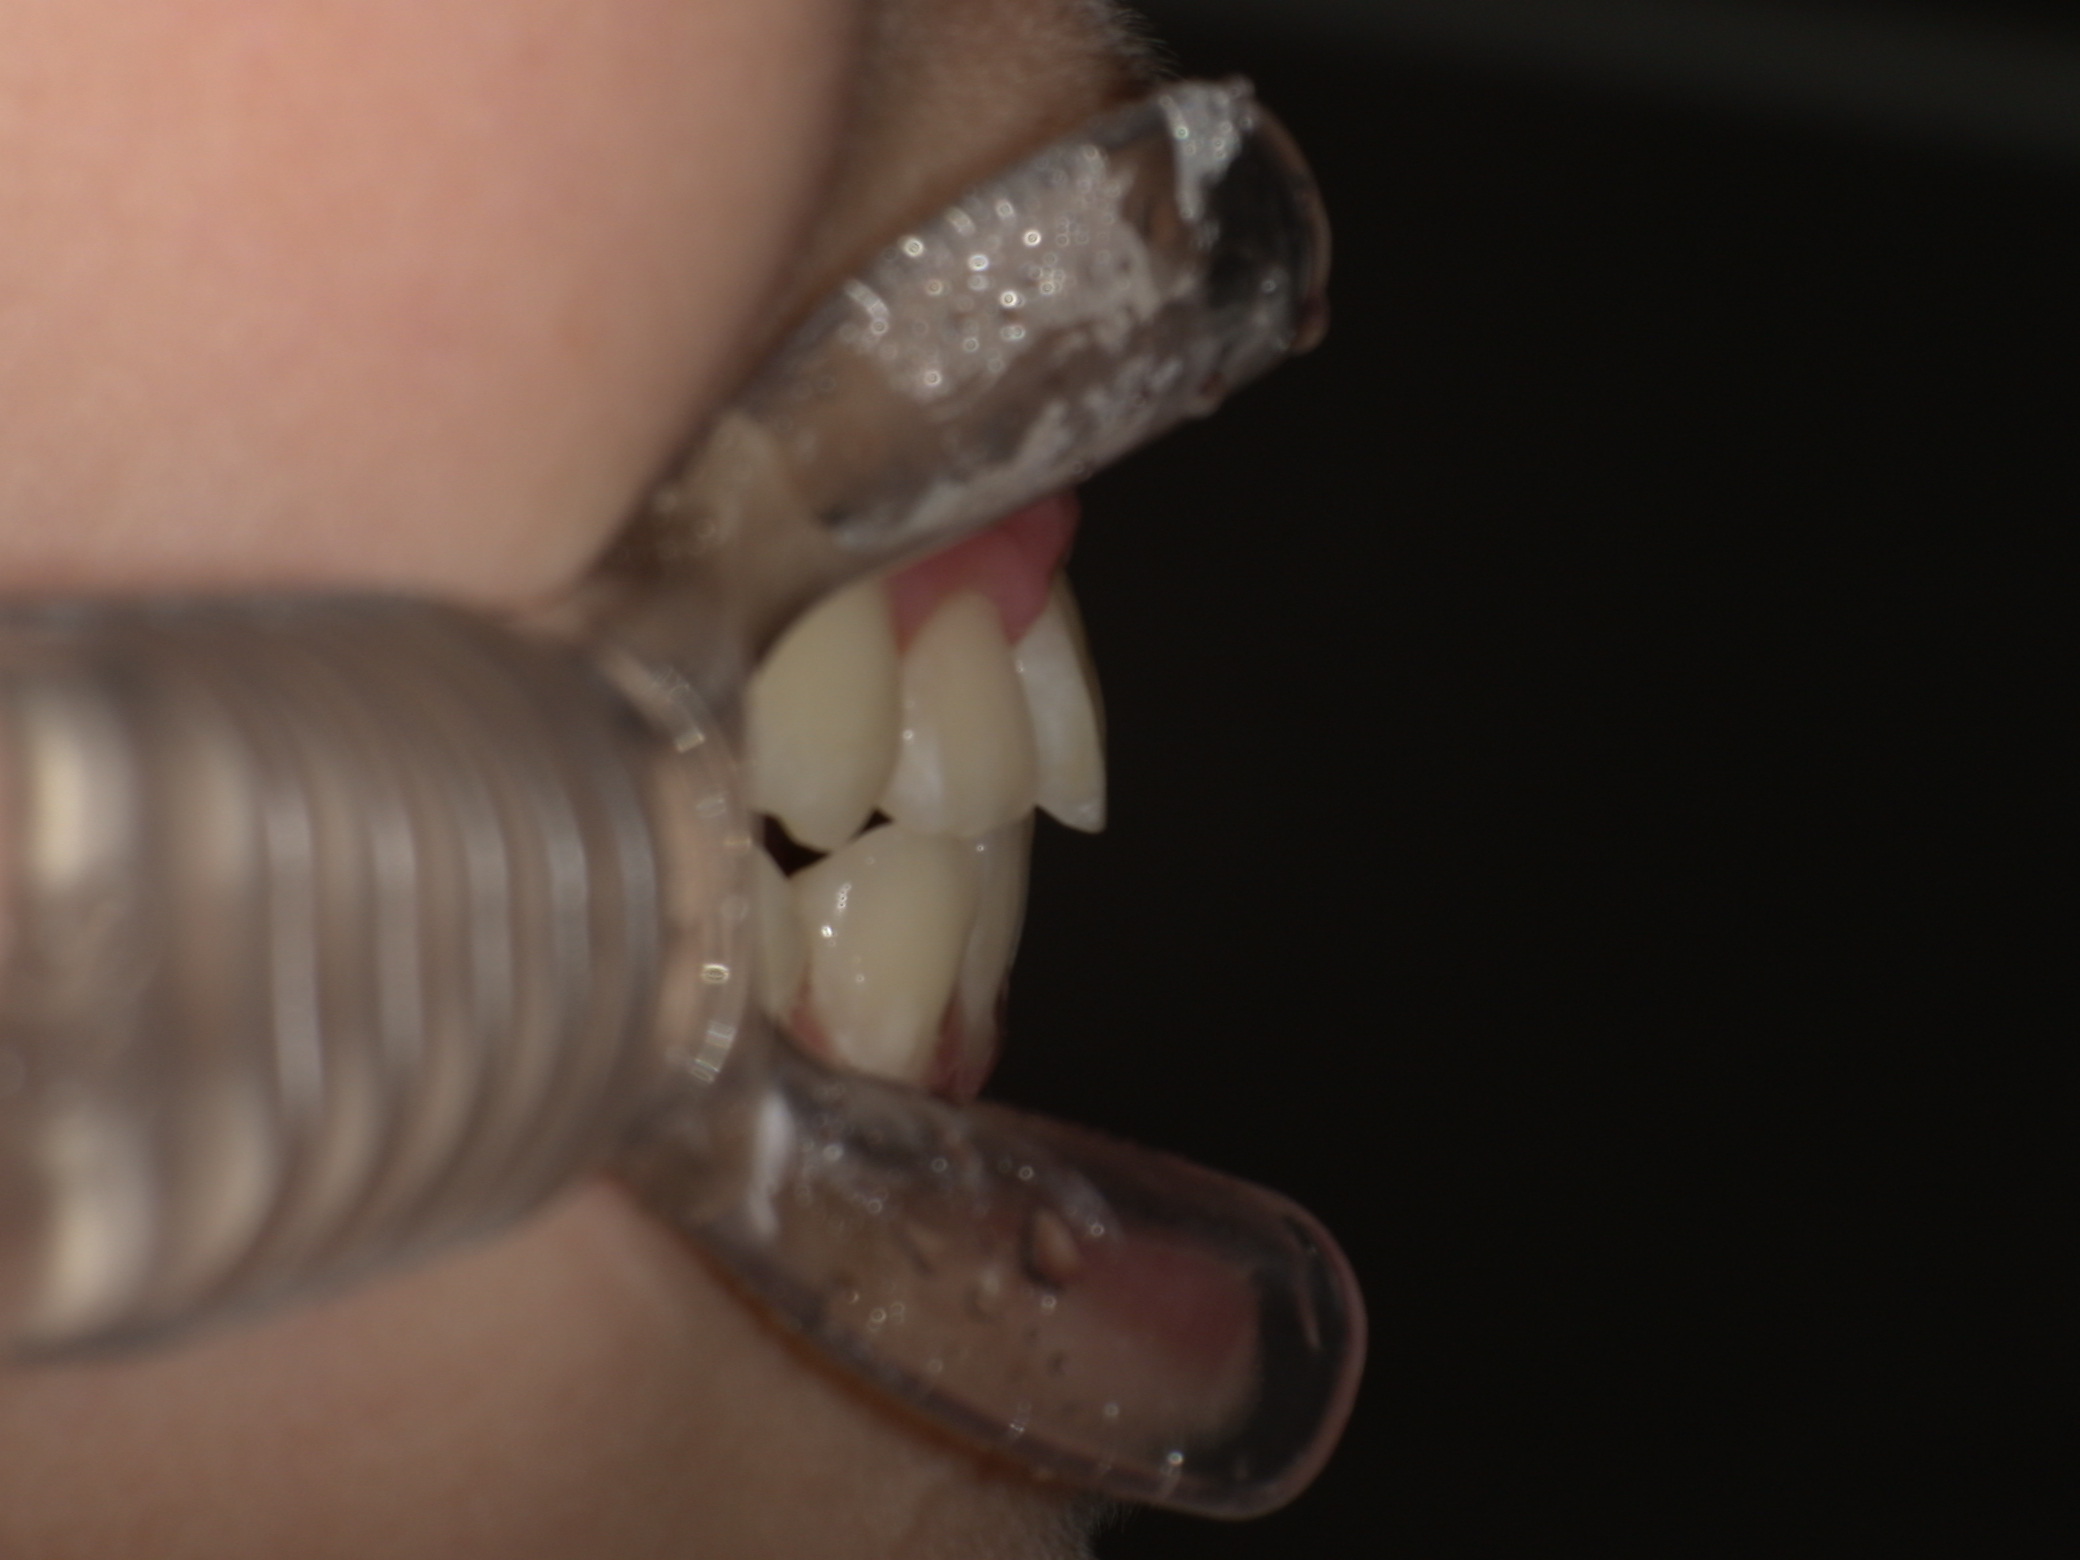

診断結果 | 6歳6か月の女児。 上下の前歯が接触せず隙間があり、開咬と診断されました。 |

治療内容 |

|

治療後の経過 | 1年11か月間の動的治療により、前歯の噛み合わせが改善されました。現在は3〜4か月ごとに定期検診を行い、上下顎の骨の成長や永久歯の萌出状況を確認しながら、本格矯正治療のタイミングを検討しています。 |

治療期間 | 動的治療期間:1年11か月 治療回数:18回 |

治療費用 | 400,000円(税別) |